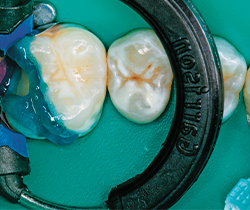

Under rubber dam isolation (Hygenic Non-Latex Dental Dam, Coltene Whaledent), the caries were removed and the teeth restored one quadrant at a time. A carbide bur was used to remove caries, followed with a diamond to bevel the cavosurface margins and finally with a round bur to excavate the deepest portion of the decay (Figs. 6-7).

Fig. 3 Fig. 4